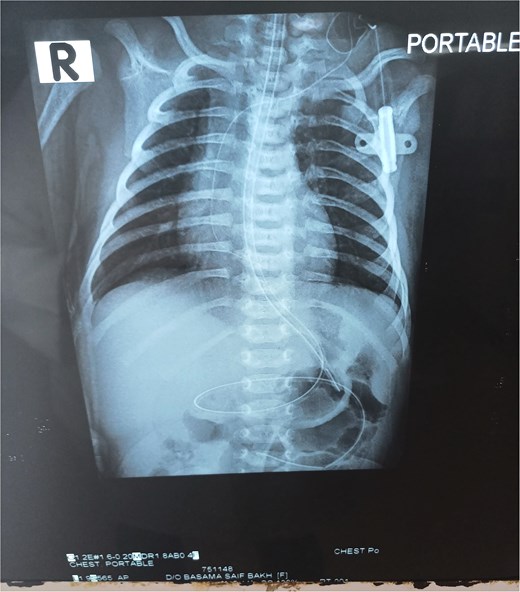

Chest X-ray was normal (Fig. 1). A water-soluble contrast meal was performed (Fig. 2) and the contrast arrested at the gastric antrum for 45 min. Then there was normal opacification of the duodenum and jejunum on follow-up films after 1.15 and 1.3 h. A complementary ultrasound (US) was done along with the contrast study and it showed a thick mucosal fold (4 mm) at the gastric antrum situated 1 cm away and on the left side of the duodenum. The pyloric canal was open and patent and had a normal wall thickness (1.5 mm) excluding hypertrophic pyloric stenosis.

The contrast study done pre-operatively showing the progression of the contrast in the digestive tract of the neonate.

To differentiate between the congenital causes of gastric outlet obstruction, upper gastrointestinal series (USG) and ultrasound are useful. Pyloric stenosis typically presents after 2 or 3 weeks and pyloric muscle thickness can be assessed by ultrasound [7]. Duodenal atresia classically show a double bubble sign on X-ray and complete arrest of contrast after pylorus [3]. Malrotation, which is an associated anomaly with GAWs in some reports, shows distal arrest of contrast [4].

For antral web, an upper gastrointestinal (UGI) series reveals persistent, sharp band-like linear defect in antrum and the “double bulb sign”, with gastric dilatation, and a delay in gastric emptying. The pylorus shows normal thickness and patent lumen. If confused with pyloric stenosis, pyloric muscle thickness is assessed [1]. In our case, the pyloric muscle thickness was normal, and together with the timing of presentation and the radiological signs, GAW was diagnosed by exclusion.